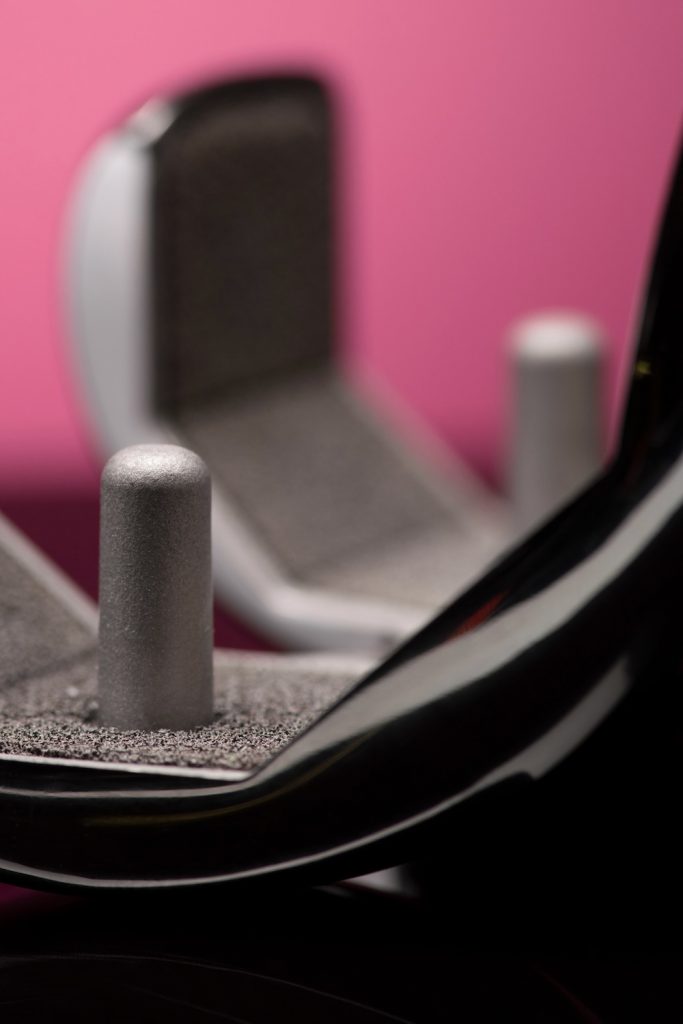

Bei der anatomischem Schulterprothese wird die Gelenkfläche des Oberarmkopfs sowie der Gelenkpfanne ersetzt. Voraussetzung ist eine intakte Muskel- und Sehnenfunktion (Rotatorenmanschette). Mehr erfahren »>

Bei der inversen Prothese tauschen Kugel und Pfanne gleichsam die Position (invers), indem man eine Halbkugel auf der Seite der ursprünglichen Gelenkpfanne montiert und die Pfanne entsprechend auf der Seite des Oberarmkopfes. Mehr erfahren »>